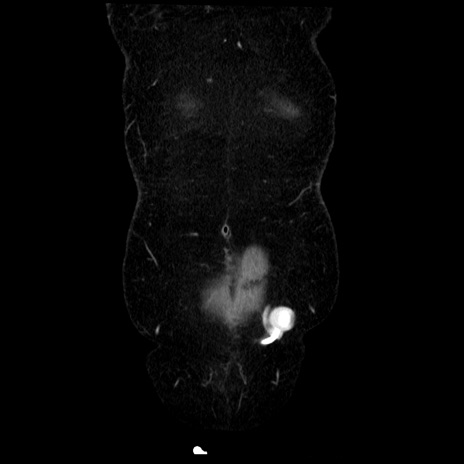

症例6(冠状断像)

【症例】50歳代女性

【主訴】下腹部痛